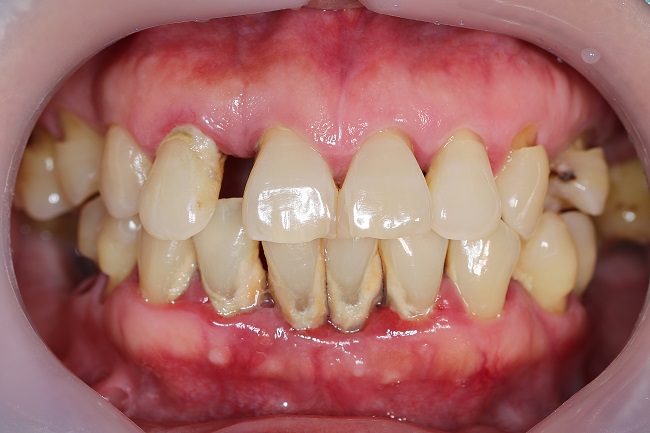

Gejala Periodontitis

Gejala periodontitis bisa beragam dan tergantung pada perkembangan peradangan yang terjadi gusi dan gigi. Namun, ada beberapa gejala atau keluhan yang umum dialami oleh penderita periodontitis, yaitu:

- Penumpukan plak dan karang pada gigi

- Gusi menyusut sehingga membuat gigi terlihat lebih panjang

- Gigi goyang atau tanggal